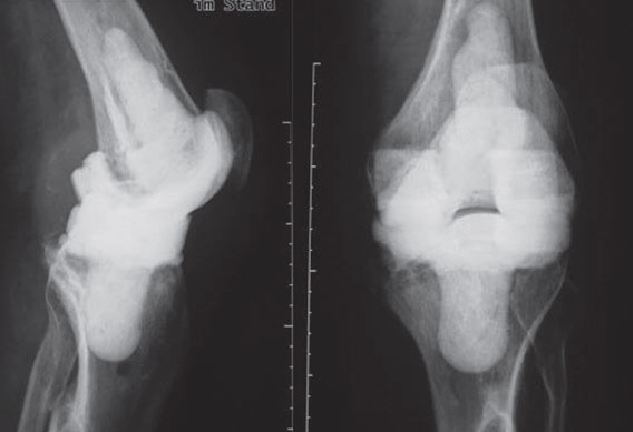

However, infections often go unnoticed for many weeks, so that removal of the prosthesis is unavoidable. Depending on the pathogen and its sensitivity, a placeholder containing antibiotics is then implanted, which remains in place for 6 weeks. Antibiotics in tablet form must then also be taken for this period. However, it is not necessary for a patient to remain in the hospital during this entire period. If home care is not possible, for example, it is also possible to organize this in close cooperation with our social services. After 6 weeks it is generally possible to reimplant a prosthesis, provided that the blood values show that the infection is under control. Antibiotics must then be taken again for 6 weeks after surgery. Which antibiotics are taken is determined in close cooperation with colleagues in microbiology and clinical pharmacology, with whom regular rounds and therapy checks are carried out. These therapeutic measures are carried out in a special area of the clinic using the most modern methods.

Infizierte HüfttotalendoprotheseKniegelenkinfektion nach EndoprotheseImplantierte Spacer nach ProthesenentfernungVorgefertigte Spacer (Platzhalter) mit Antibiotika